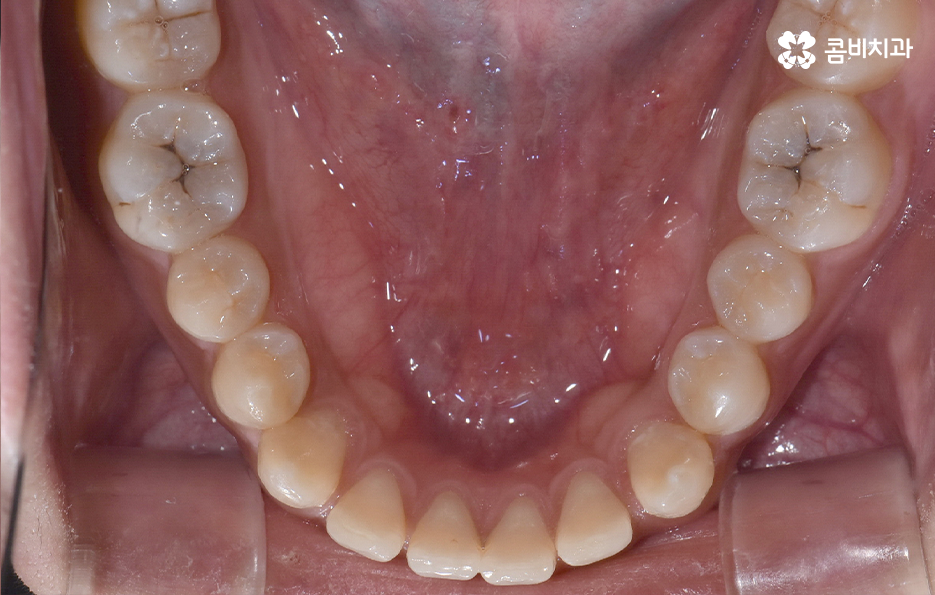

그나마 다행인 점은 앞니만교정을 하더라도 치아의 교합이나 골격적인 부분, 얼굴형 등에 있어서 큰 지장은 없던 경우였는데요. 물론 아랫니가 다소 벌어져 있기 때문에 전체교정을 하면 더 좋은 결과를 얻을 수 있었겠지만 환자분의 니즈에 있어서 앞니만교정을 빠르게 원했던 사례이기 때문에 앞니 부분의 과잉치 발치 후 앞니만교정을 부분적으로 진행했어요

과잉치로 인해 말그대로 치아의 정상 범위 이상으로 치아가 배열되기 때문에 다른 치아의 배열에도 악영향을 주는 경우가 많지만 위 환자분의 케이스의 경우에는 치열 자체는 전체적으로 가지런한 편이라는 점과 특히 턱뼈가 넓은 편이라는 점에서 전체교정을 하지 않았어도 환자분이 원하는 치료의 목표는 달성할 수 있었어요